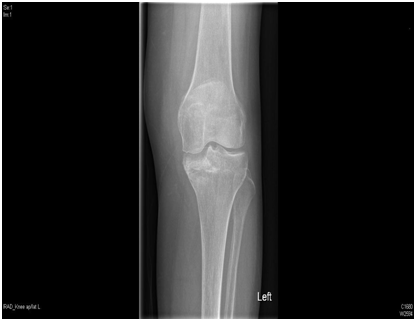

We present a 77 years old Caucasian female with spontaneous onset of pain in both knees for several weeks before presenting to the casualty then to our fracture clinic. There was no history of trauma. The patient is known to have Rheumatoid arthritis (RA) for over 30 years and has been on Bisphosphonate treatment (Alendronate) for over 24 months following the diagnosis of osteoporosis by DEXA scan. Plain radiographs showed subtle linear areas of sclerosis bilaterally in her proximal tibiae (Figure 1 & 2). Magnetic resonance imaging confirmed the presence of extra-articular linear high signal intensity change on T1, T2 with surrounding marrow edema consistent with insufficiency fractures in these areas as well as her right distal femur (Figure 3). These fractures were treated successfully with activity modification and weight bearing in a hinge knee brace as symptoms allows for six weeks along with physiotherapy input. Alendronate was stopped and Teriparatide (Recombinant PTH) was started.

Figure 3 Magnetic resonance imaging coronal and sagittal T2 showing a linear signal change in both the proximal tibia and right distal femur with surrounding bone odema.